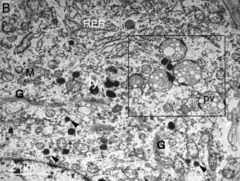

Ultraestructura

Con la microscopía electrónica las neuronas magnocelulares (MagCN) muestran abundantes estructuras membranosas, numerosas mitocondrias, retículo endoplásmico dilatado, aparato de Golgi bien desarrollado y gránulos secretorios de centro denso, todo lo que evidencia la actividad de biosíntesis dentro de estas neuronas.[5] El núcleo supraóptico (SON) está muy vascularizado. Los capilares se encuentran dispersos a través de este núcleo y se observan cerca de las neuronas magnocelulares.[5]